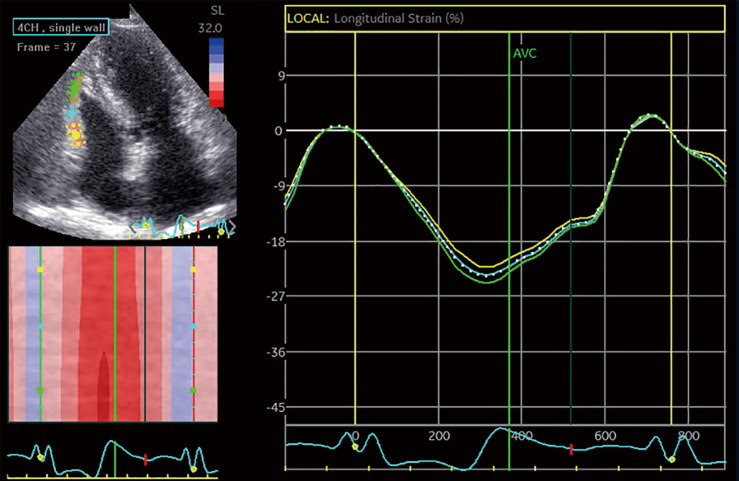

本研究探讨了左心房(LA)储液池应变在左侧心力衰竭(HF)情况下作为右室(RV)功能障碍(RVD)的独立决定因素的潜力。我们在2021年至2023年间从中国医科大学第一医院招募了301例HF患者(年龄61.1±10.7岁,男性71.1%),包括减少(47.8%)和保留射血分数(EF)(52.2%)表型的代表性样本。每位参与者都接受了全面的经胸超声心动图检查。常规超声心动图测量左室(LV) EF和肺动脉收缩压(PASP),二维散斑跟踪超声心动图量化左室整体纵向应变(LVGLS)、左室储层应变和左室游离壁应变。该队列显示RVD患病率为48.5%(定义为RV游离壁应变< |20%|)。RVD与较高的体表面积[比值比(OR) 12.01]和PASP (OR 1.02),较低的LVEF (OR 0.92), LVGLS (OR 1.35)和LA库菌株(OR 0.82)相关(均P值)

This study examined the potential of left atrial (LA) reservoir strain to be an independent determinant of right ventricular (RV) dysfunction (RVD) in the context of left-sided heart failure (HF). We recruited 301 patients with HF (age 61.1±10.7 years; 71.1% male) from The First Hospital of China Medical University between 2021 and 2023, comprising a representative sample of both reduced (47.8%) and preserved ejection fraction (EF) (52.2%) phenotypes. Each participant underwent comprehensive transthoracic echocardiography. Conventional echocardiography measured left ventricular (LV) EF and pulmonary artery systolic pressure (PASP), and two-dimensional speckle tracking echocardiography was applied to quantify LV global longitudinal strain (LVGLS), LA reservoir strain, and RV free wall strain. The cohort demonstrated a 48.5% prevalence of RVD (defined as RV free wall strain < |20%|). RVD was associated with higher body surface area [odds ratio (OR) 12.01] and PASP (OR 1.02), lower LVEF (OR 0.92), LVGLS (OR 1.35), and LA reservoir strain (OR 0.82) (all P values <0.05). Critically, LA reservoir strain (OR 0.83; P<0.001) remained independently associated with RVD even after adjustments were made for age, sex, body surface area, atrial fibrillation, diabetes, hypertension, coronary artery disease, LVEF, LVGLS, and PASP. Thus, in left-sided HF, LA reservoir strain independently predicts RVD irrespective of LVEF or PASP, highlighting the critical role of LA function in RVD.